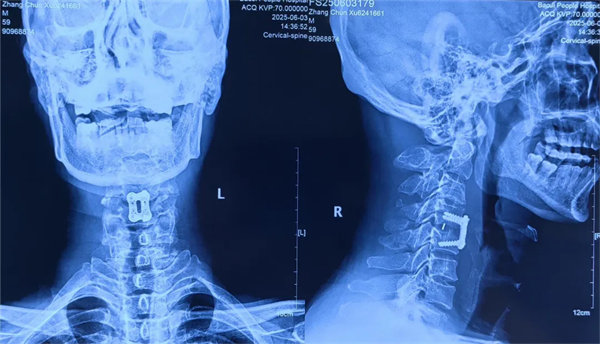

患者受傷后曾在外院接受保守治療,但肢體麻木癥狀持續(xù)存在。轉(zhuǎn)入我院時,頸椎CT及MRI顯示:頸4/5椎骨折脫位,脊髓受壓明顯,若不手術(shù)治療,可能面臨永久性神經(jīng)功能障礙。我院骨四科團(tuán)隊(duì),制定了前路ACDF手術(shù)方案:通過頸前側(cè)入路,切開復(fù)位、切除椎間盤,解除脊髓壓迫,同時植入融合器、鈦板固定,重建頸椎正常序列及穩(wěn)定性。術(shù)后患者麻木感消失,復(fù)查顯示頸椎序列恢復(fù)良好,目前已康復(fù)出院。

術(shù)后